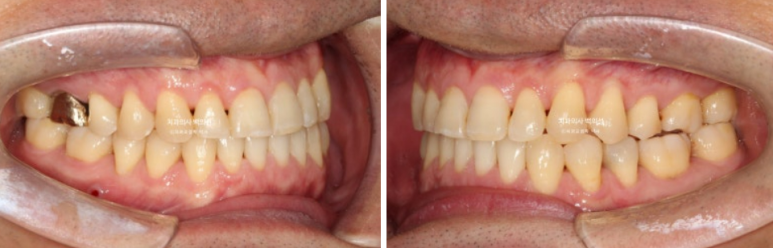

23.12~25.03